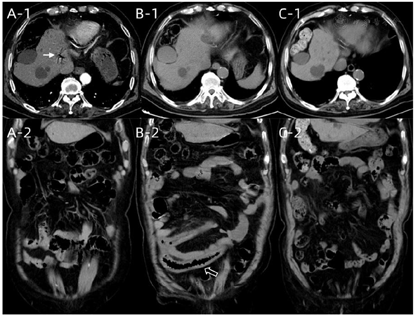

化验检查:CRP 1.04 mg/L,WBC 6.62×109/L,NEU% 77.7%↑,D-dimer 2.41 mg/L FEU↑,K 3.87 mmol/L,Na 138.5 mmol/L。急诊腹部增强CT(图1A):部分小肠管壁略增厚,周围脂肪间隙略显浑浊,增强扫描动脉期肠管管壁强化程度略低于周围肠管;区域肠系膜静脉血管内可见少许气体密度影;肠系膜上静脉及肝内门脉部分小分支内可见气体密度影。肠系膜上动脉管腔呈重度狭窄。诊断:急性小肠缺血;肠系膜上动脉狭窄(近闭塞);肝门静脉积气;冠脉搭桥术后;高血压3级;高脂血症。考虑肠系膜上动脉血栓栓塞可能性大,急诊收入血管外科,予依诺肝素钠3000 IU皮下注射抗凝、前列地尔及罂粟碱静脉点滴扩血管治疗。